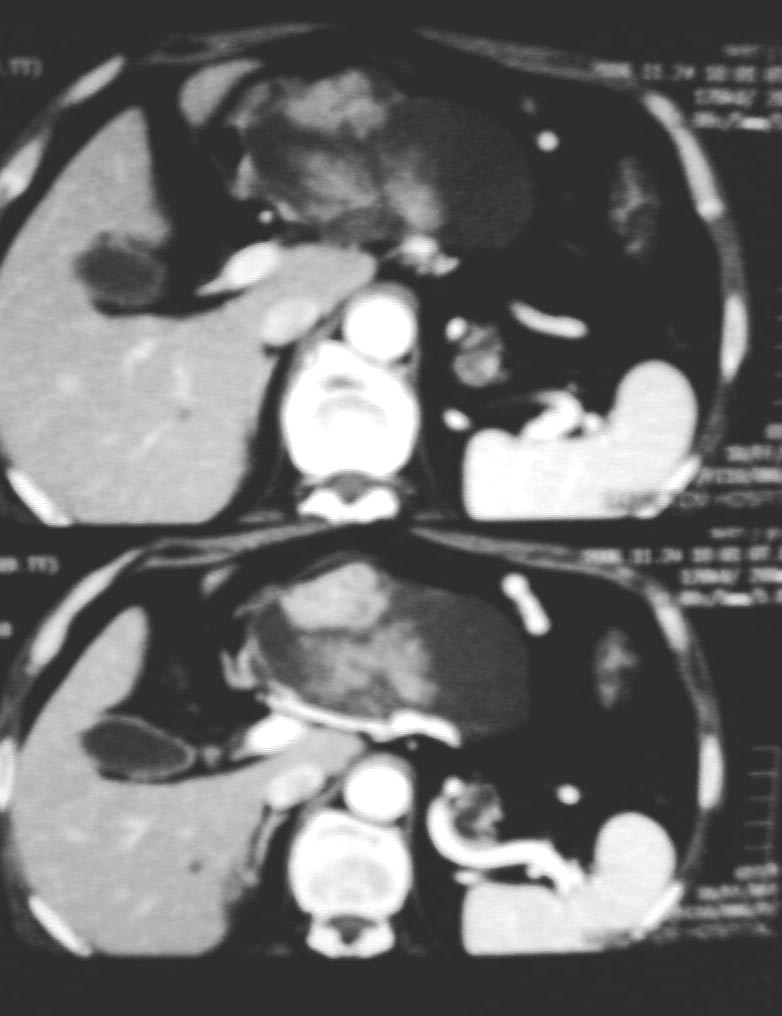

上腹部不适半年左右,体检此区压痛,精神状态很好,谢各位给个意见!

与中国医学影像网中“今日病例”(12-2)类似——胰管乳头状粘液瘤。

考虑胰腺黏液腺癌.低度恶性.

考虑胰管乳头状粘液瘤

胰腺占位病灶

1与中国医学影像网中“今日病例”(12-2)类似——胰管乳头状粘液瘤

2考虑胰腺黏液腺癌.低度恶性.